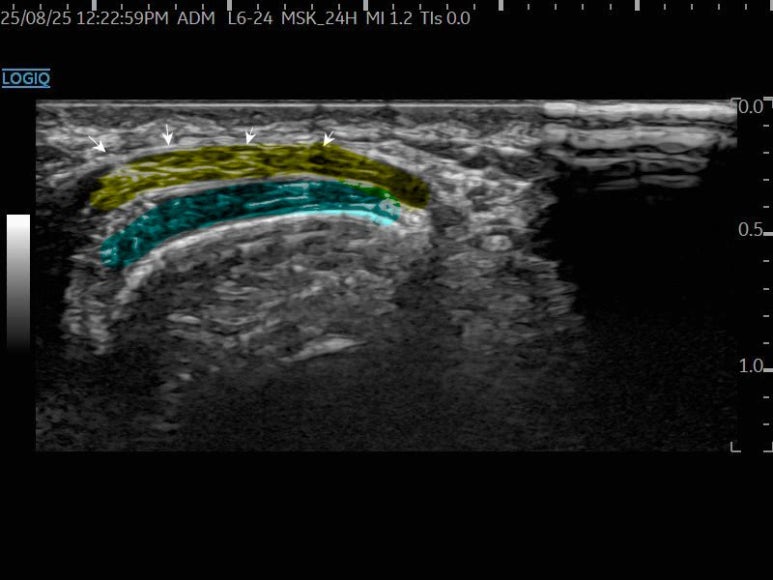

노란색의 첫번째 구획이

파란색의 두번째 구획 위에 겹쳐있는 모습을

실시간으로 관찰할 수 있습니다.

*바로 이 부위에서

마찰로 인해 염증이 생기는 것입니다.

드퀘르벵 질환 환자에게서

손목 통증이 잘 호전되지 않을때,

교차증후군 위치에서

1구획에 먼저, 1차 시술을 하고요.

조금 더 안쪽으로 진입해서,

2구획의 힘줄집에이어서 2차 시술을 진행합니다.

시술 후에,

1구획, 2구획 모두

적절하게 시술이 잘 되었음을 확인할 수 있는데요.

이러한 방법은1번의 진입으로 2군데에 접근해1타2피의 치료효과를 내는 것이죠.